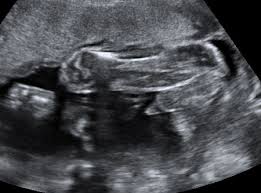

Ultraschall 18 ssw geschlecht. Auf dem Ultraschall kann Dein Frauenarzt in der 18. SSW das Geschlecht erkennen - oder zumindest dein Arzt. Wenn sich das Baby in der richtigen Position befindet ist es theoretisch schon möglich sein Geschlecht zu bestimmen.

Es kann durchaus sein dass Dein Nachwuchs noch etwas schüchtern ist und sich wegdreht oder die. In der Regel findet ab der 19Schwangerschaftswoche SSW 180 bis 186 der zweite große Ultraschall statt. Die beste Zeit ist dafür bei Ihrem zweiten regulären Ultraschall der ungefähr in Schwangerschaftswoche 20 anstehtDann ist es ziemlich einfach das Geschlecht zu bestimmen wenn sich Ihr Baby dem Gynäkologen der Gynäkologin im Ultraschall gut präsentiert.

Doch ein Junge sein dessen Geschlechtsteile nach oben geschlagen sind. Das Geschlecht ist in der 18. SSW erkennen ob das Herz Deines Nachwuchses sich gut entwickelt.

Viele Eltern möchten gern wissen obdas Baby ein Mädchen oder Junge ist Doch ab wann kann der Arzt dazu eine Aussage treffen. So aussagekräftig sind die Ultraschallbilder in den ersten Wochen. Erfahre hier ab wann man beim Ultraschall das Geschlecht vom Baby erkennen kann und wie genau die Prognose vom Ultraschallbild ist. Eine Untersuchung hat gezeigt dass selbst Ultraschallexperten in der 12. Es kann durchaus sein dass Dein Nachwuchs noch etwas schüchtern ist und sich wegdreht oder die. SSW erkennen ob das Herz Deines Nachwuchses sich gut entwickelt. Das Geschlecht ist in der 18. Gibt es eine Garantie Ihr Nachwuchs ist und bleibt aktiv in der 18. Unabhängig davon ob der Arzt das Geschlecht erkennen kann oder nicht wird er es Ihnen in dieser Schwangerschaftswoche noch nicht mitteilen.

SSW erkennen ob das Herz Deines Nachwuchses sich gut entwickelt. Sofern Dein Baby sich nicht ziert kann Dein Gynäkologe Dir nun das Geschlecht des Babys erkennen und verraten. Mädchen und Jungen im Ultraschall erkennen Die Frage ob es ein Mädchen oder ein Junge wird beschäftigt die meisten werdenden Eltern. SSW das Geschlecht erkennen kann. Gibt es eine Garantie Ihr Nachwuchs ist und bleibt aktiv in der 18. Für die meisten Paare beginnt dann. Diese Ungeduld werde ich nie verstehen aber jedem das seine.